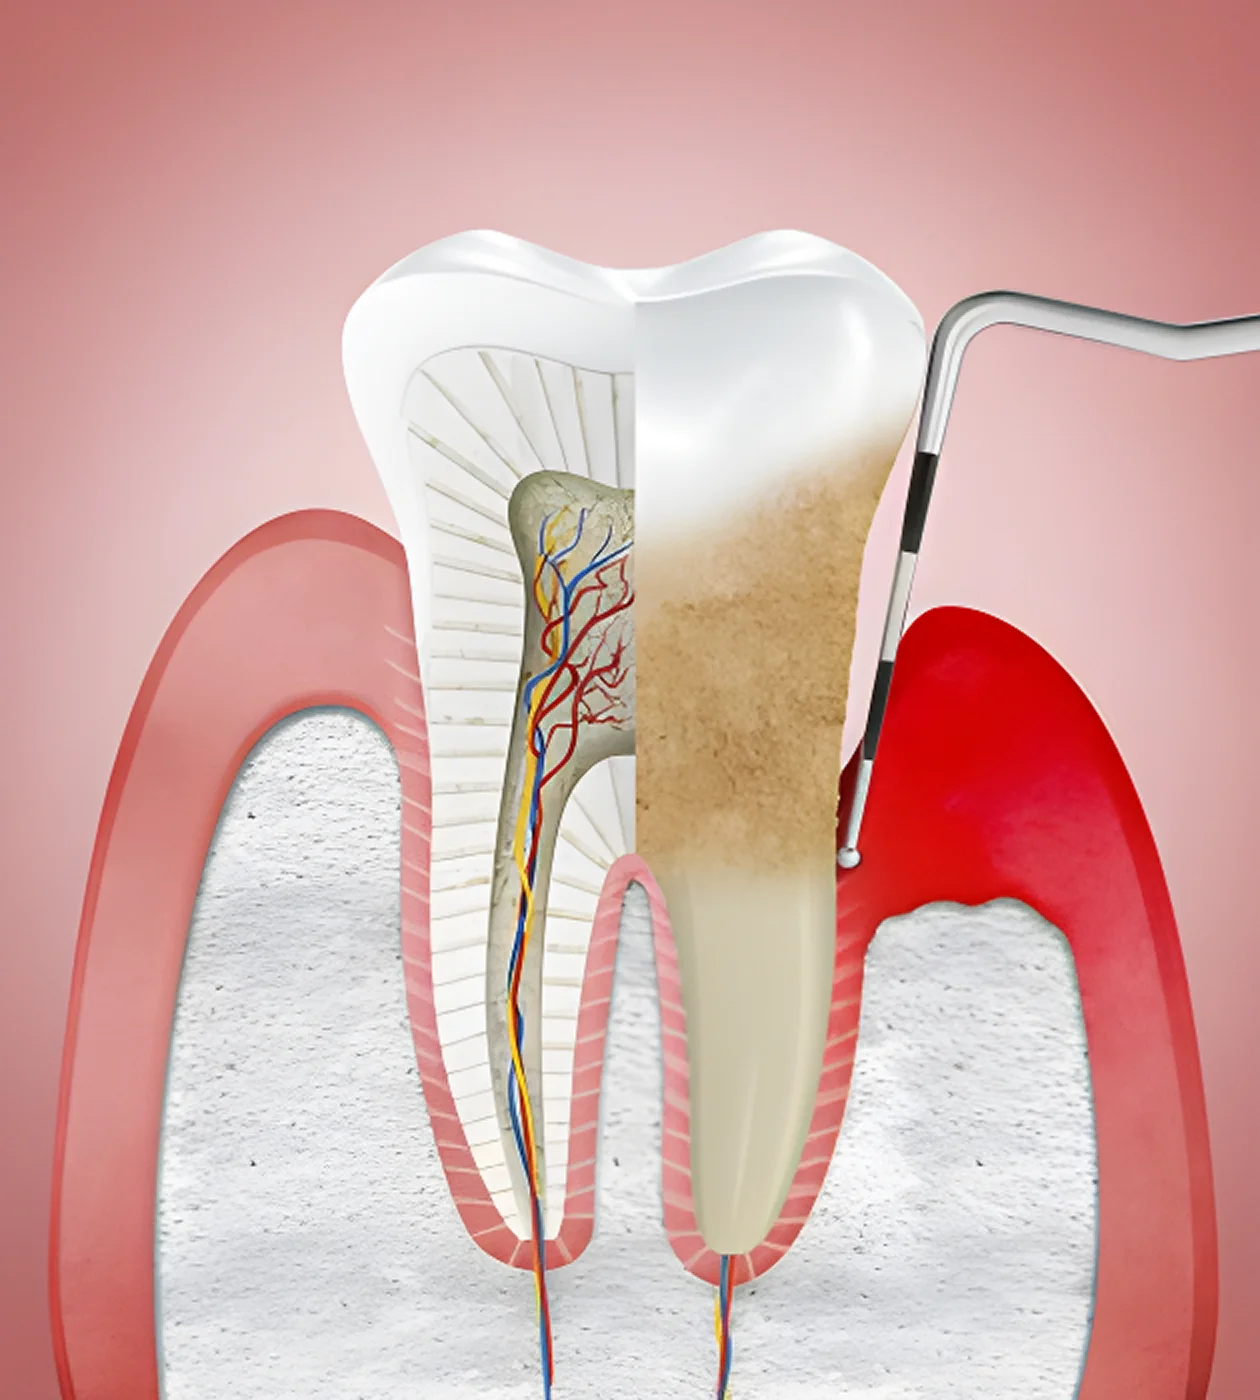

ПАРАДОНТОЛОГІЯ

Лікування захворювань ясен та парадонта (гінгівіт, парадонтит, парадонтоз). Терапія згідно протоколів доказової медицини.

Професійна гігієна по протоколу SRP

Глибоке очищення зубів і ясен від нальоту та каменю для профілактики захворювань пародонту та запобіганню розвитку карієса.